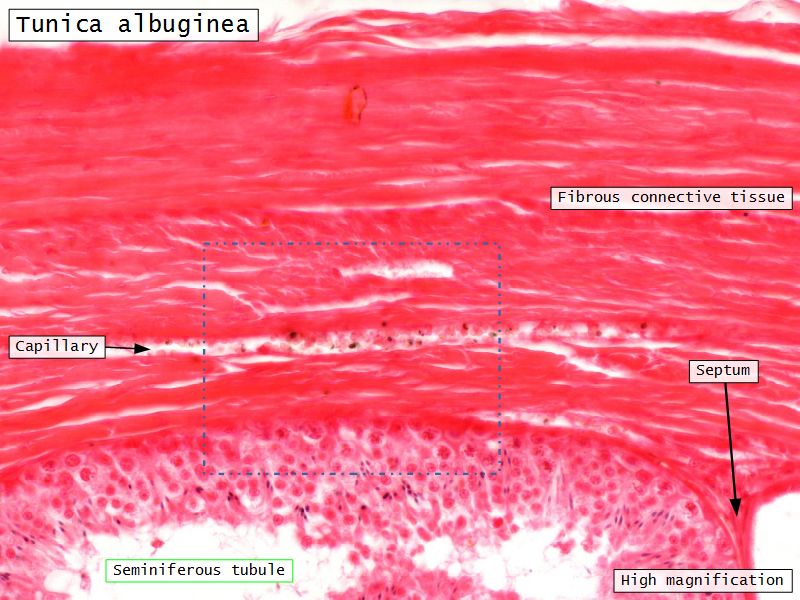

Tunica albuginea

- Thick fibrous CT capsule

- Forms septae

- Divide testis into lobuli